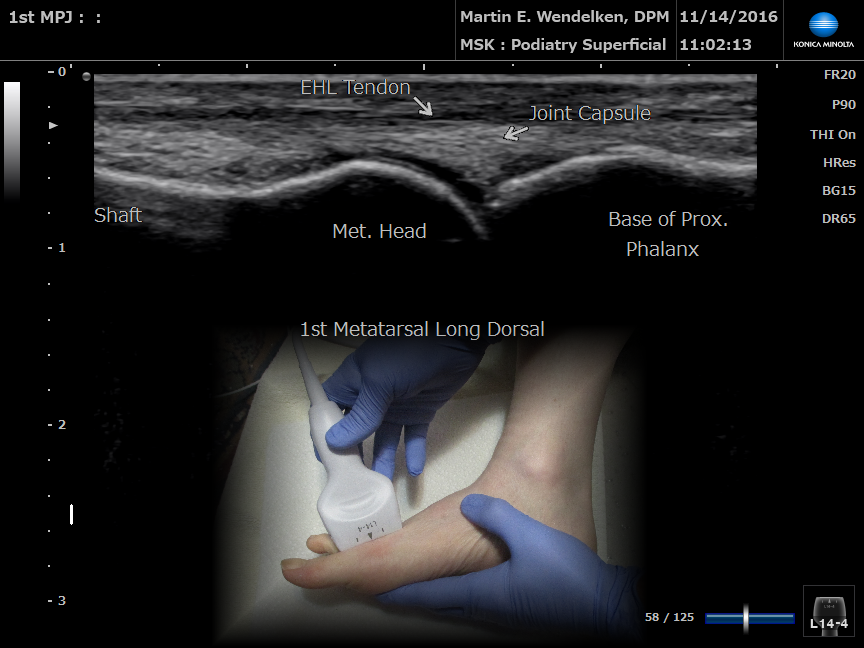

• Image 1: 1st Metatarsal Phalangeal Joint